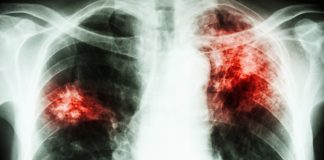

TUBERCULOZA UCIDE PE TACUTE!